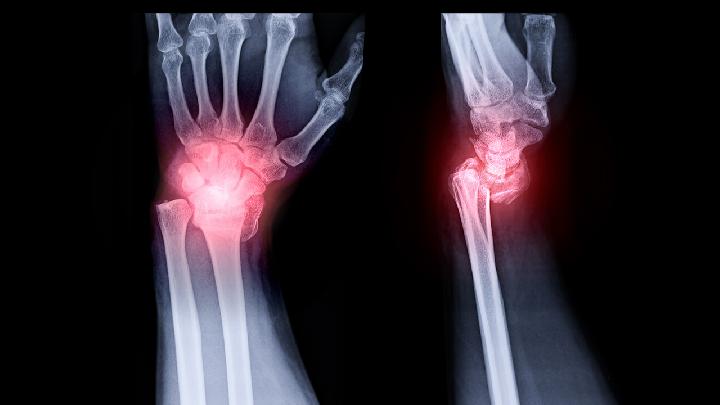

腱鞘炎是一种常见的手外科疾病,很多人由于经常性的活动手部或者活动手部时用力太大,导致肌腱和腱鞘的过度摩擦,从而容易诱发腱鞘的损伤性炎症,引起肿胀,产生腱鞘炎。